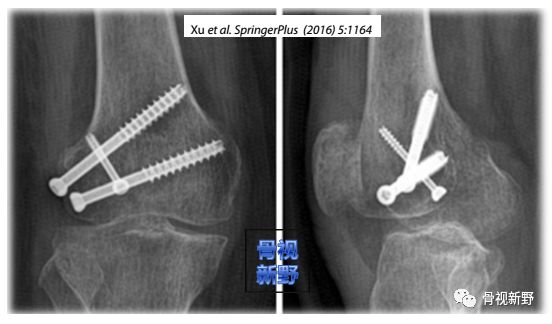

Xu(2016)等人以2枚6.5mm半螺纹空心螺钉从侧方非关节面打入,再以另一枚小直径(3.5mm或4.5mm)螺钉自髁间窝非关节面向前外侧(或前内侧)打入,形成三角形交叉螺钉固定的新方法治疗11例Hoffa骨折,与2枚平行加压固定的传统螺钉固定方式对比研究发现,该新方法与传统固定方法一样有效。

III型骨折线呈斜形,骨折块较大,髁间窝非关节面部分比较大,足以加打螺钉,因此,Xu等人(SpringerPlus,2016;5:1164)认为,他们创新的三角交叉螺钉固定新术式(图文详见前文)比较适合III型骨折。